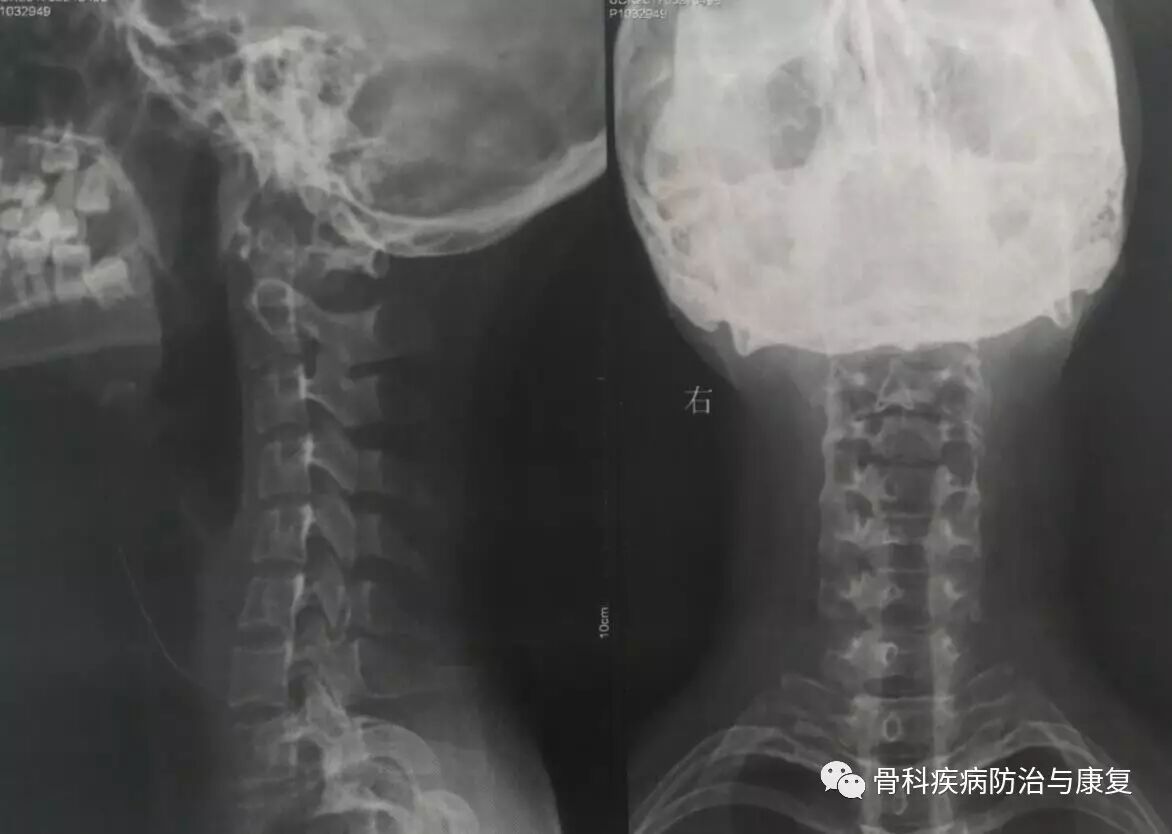

颈椎反弓症状,颈椎反弓最佳枕头

症状的描述,我给小黄拍了一个颈椎的x光片,x诊断结果提示: "颈椎反弓"

颈椎反弓真人图片

颈椎反弓图片

颈椎反弓图片正常

颈椎反弓图片对比